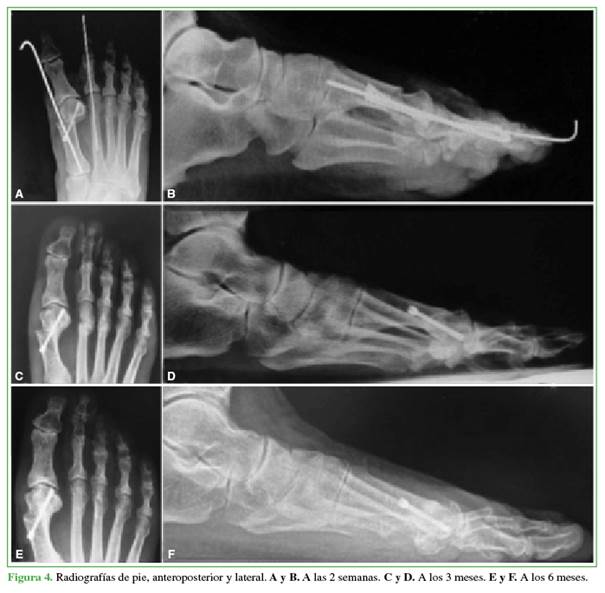

Los pacientes fueron evaluados clínica y radiológicamente antes de la cirugía, a las 3 semanas, a los 3 meses, o hasta constatar la consolidación (Figuras 3 y 4).

Podemos decir que la incidencia de dedo flotante en nuestros pacientes (31%) es similar a la publicada en otros artículos.8,10 La incidencia de reluxación posquirúrgica en esta serie fue del 13%. Esta cifra es comparable con la de otras series publicadas (12-15%).7,20 En la mayoría de los casos, las reluxaciones fueron asintomáticas. El único caso sintomático se resolvió con una osteotomía percutánea de la primera falange (Figuras 4 y 5). Los resultados funcionales posoperatorios fueron satisfactorios con una media de la escala de la AOFAS de 86 puntos (rango 63-90).